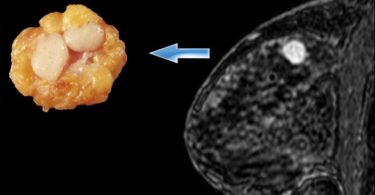

Удаление фиброаденомы молочной железы представляет собой безопасную процедуру, необходимую для восстановления здоровья органа. Несмотря на то что эта категория опухолей редко переходит в разряд злокачественных, требуется своевременная их ликвидация...

Фиброаденома молочной железы: удалять или нет? Этот вопрос тревожит очень многих женщин. Прежде чем на него ответить, стоит разобраться, что это за заболевание. Данное новообразование доброкачественного характера, но это не значит, что оно не...

У молодых женщин иногда появляется фиброаденома молочной железы, лечение без операции которой является поводом для многочисленных дискуссий. Каждая третья представительница слабого пола сталкивается с неприятными или опасными образованиями груди...

Фиброаденома молочных желез – гормонозависимое, имеющее доброкачественный характер течения образование, которое развивается из соединительной ткани. Имеет высокую подвижность и ограниченную округлую форму. С кожей опухоль не срастается, не...